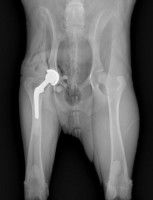

Les prothèses de hanche pour chien sont indiquées essentiellement dans des cas sévères de dysplasie de la hanche, qui est une atteinte de l’articulation de la hanche dans laquelle la tête du fémur n’est pas bien adaptée à la cotyle, c’est-à-dire la cavité de la hanche qui lui correspond. Cette affection héréditaire peut concerner tous les chiens, mais certaines races y sont prédisposées, notamment les grandes races de chien, ainsi que quelques moyennes (Rottweiler, Terre-Neuve, Siberian Husky, etc.).

Il existe également d’autres situations qui peuvent rendre nécessaires la pose d’une prothèse totale de hanche, comme une luxations, une fracture ou la maladie de Legg-Calvé-Perthes (nécrose progressive et douloureuse de la tête du fémur).

La première prothèse de hanche pour chien fut posée en 1957. Depuis, plus de 40.000 chiens dans le monde ont bénéficié d’un tel dispositif. Les vétérinaires proposent cette solution lorsque les traitements (infiltrations, anti-inflammatoires...) ont échoué, après une destruction importante de la hanche suite à un traumatisme, ou encore dans le cas d’une maladie vasculaire résultant d’un cas de Legg-Calvé-Perthes.